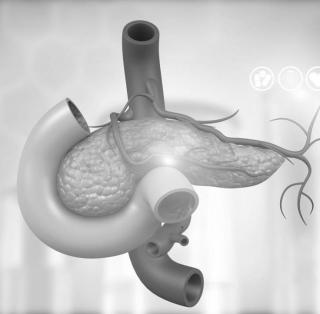

Фотографии медицинских исследований инсулиномы и синдрома Триады Уиппла